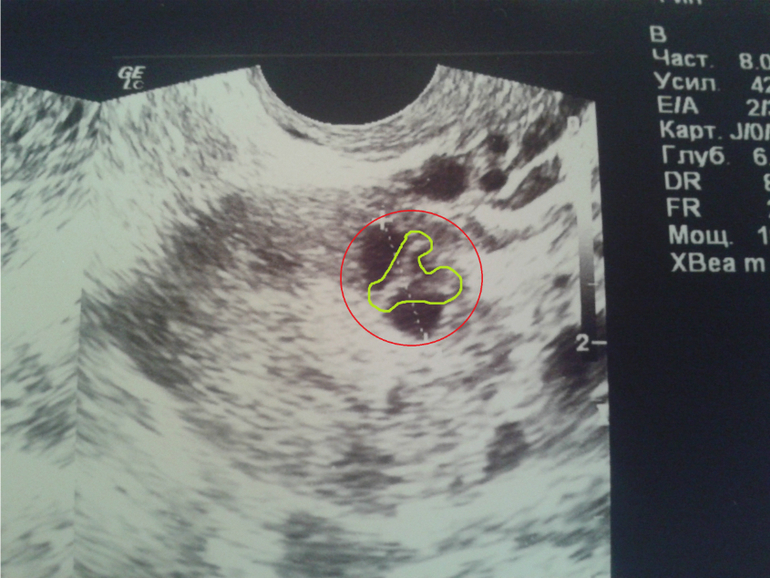

а он ёпа мама стал какой то странный, см.фото

внутри какие то перегородки появились, да не одна, а две, т.е. он как бы состоит из 3-х фолликулов, габаритный размер 11,6мм, эндик 10,5мм

жидкость в незначительном количестве